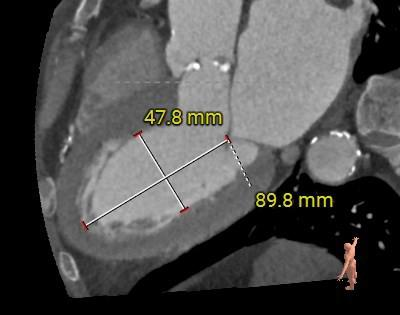

冠脉阻挡风险及左室大小评估

3.左心室舒张期前后径59mm,术中发生恶性心律失常风险大,预装瓣膜,备自动除颤仪和体外循环。

左室前后径56mm,室间隔厚度13mm,左室后壁厚度11mm,室壁运动幅度减低,EF:50%,FS:26%,SV:105ml,EDV:159ml,ESV :79ml,SV :80ml 。